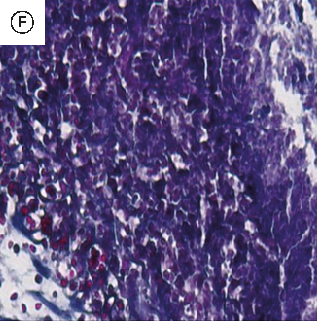

Figure 7

The Healing Effect of Aloe Vera Gel on Acetic Acid-Induced Ulcerative Colitis …